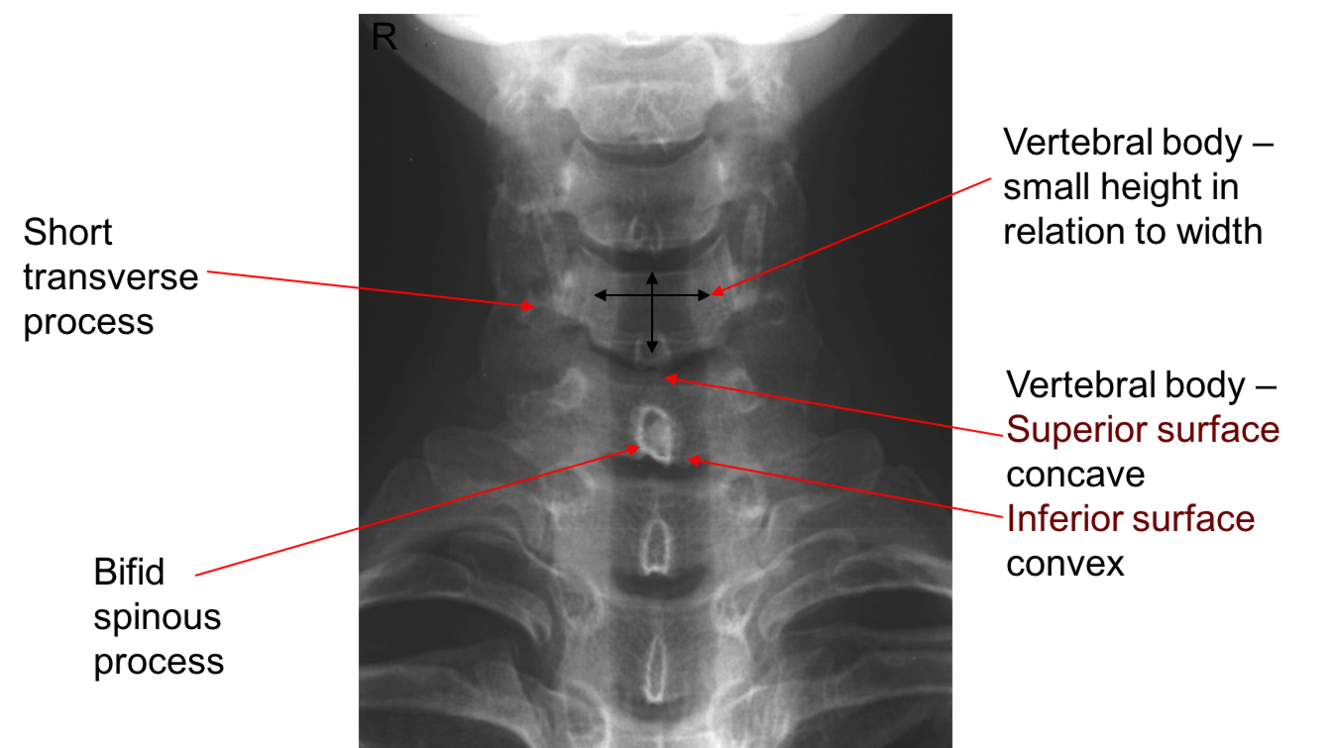

Label image